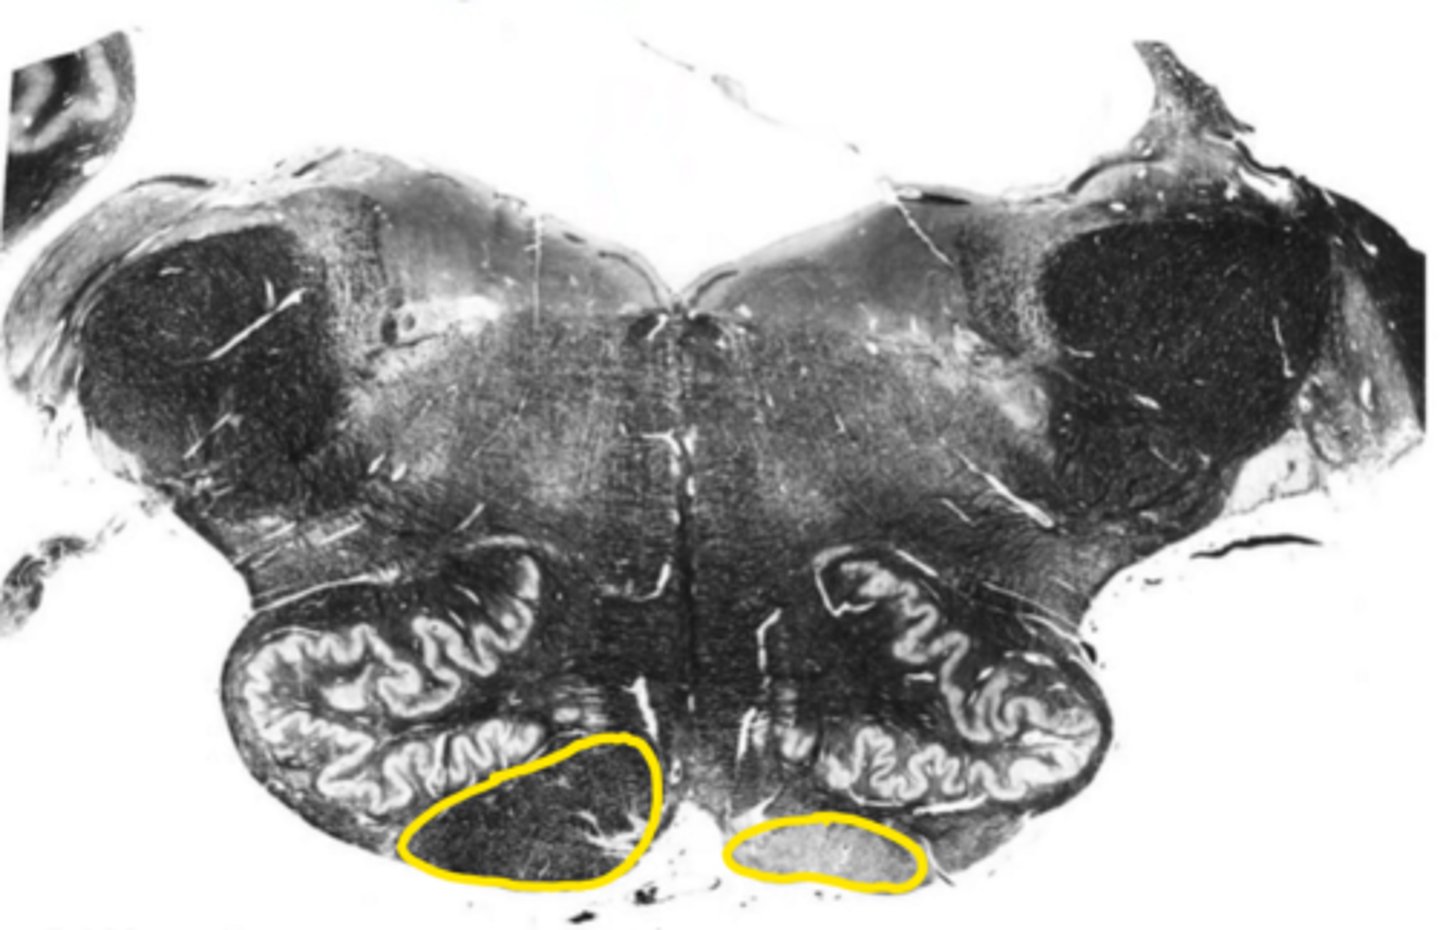

closed medulla

ID the brainstem level